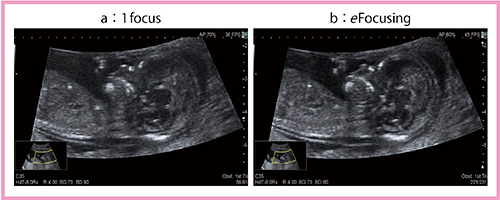

1.eFocusingの有用性

新しい送受信技術である“eFocusing”を適用すれば,浅部から深部まで画面全体にフォーカスの合った画像が得られる。eFocusingは受信ビーム領域が広く,複数の送信ビームから得られる受信ビームの中で,最も高輝度な部分を合成するため,SN比の高い鮮明な画像が描出できる。

図1は,胎児の頸部浮腫(NT)計測画像であるが,1点Focus(a)と比較し,eFocusing(b)では深さ方向全体にフォーカスが合っており,鼻先のラインや鼻骨の繊細さ,間脳の抜けが良好に描出されている。また,フレームレートも1点Focusが36fps,eFocusingが45fpsと,高フレームレートとなっている。eFocusingにより,フォーカスを合わせている間に胎児が動いてしまうという煩わしさも解消すると思われる。

図1 胎児のNT計測画像におけるフォーカスの違い